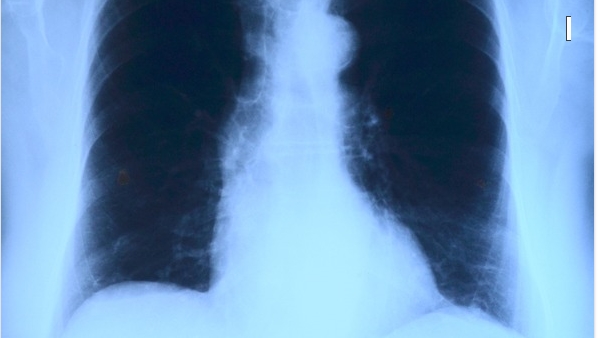

폐암 환자 생존율 두 배로 증가시켜

폐암에 대한 최선의 치료법이 지속적인 이점을 계속 보여주고 있다는 새로운 임상 실험 결과가 나왔다.

최근 연구에서 일부 고형 종양 폐암에 대한 1차 치료법의 표적 약물인 타그리소(osimertinib)가 폐암이 EGFR(epidermal growth factor receptor) 유전자의 돌연변이에 의해 유발되는 초기 단계 환자들의 무병 생존율을 거의 두 배 증가시키는 것으로 보고되었다.

4년간의 추적 관찰 결과, 무병 생존율은 타그리소 그룹에이 73%인데 반해 위약을 투여 받은 환자에서는 38%였다.

알약으로 복용한 이 약물은 위약에 비해 환자의 암 재발을 절반으로 줄였다(27% 대 60%). 특히 환자들의 다른 신체 부위로의 암전이 가능성도 적었다.